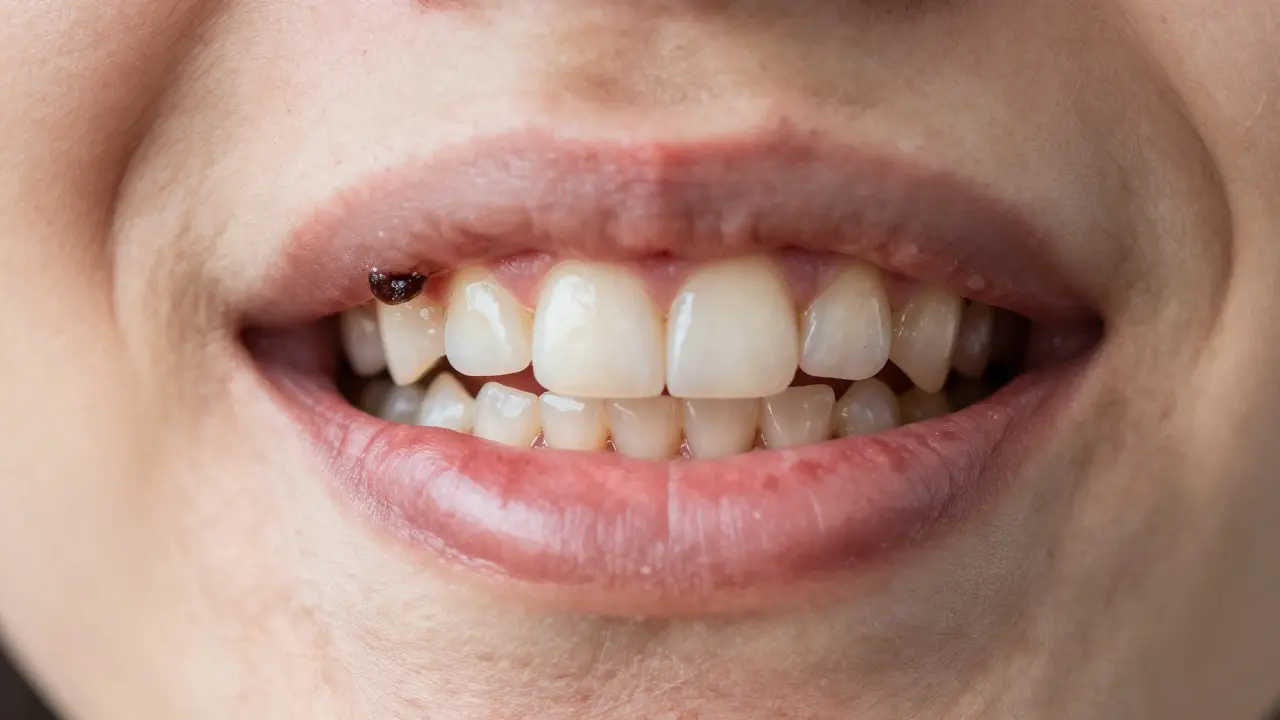

1. Černá nebo hnědá čára u dásně - hlavně na předních zubech nebo na vnitřní straně dolních řezáků. To není „zabarvení“ od čaje. To je káž.